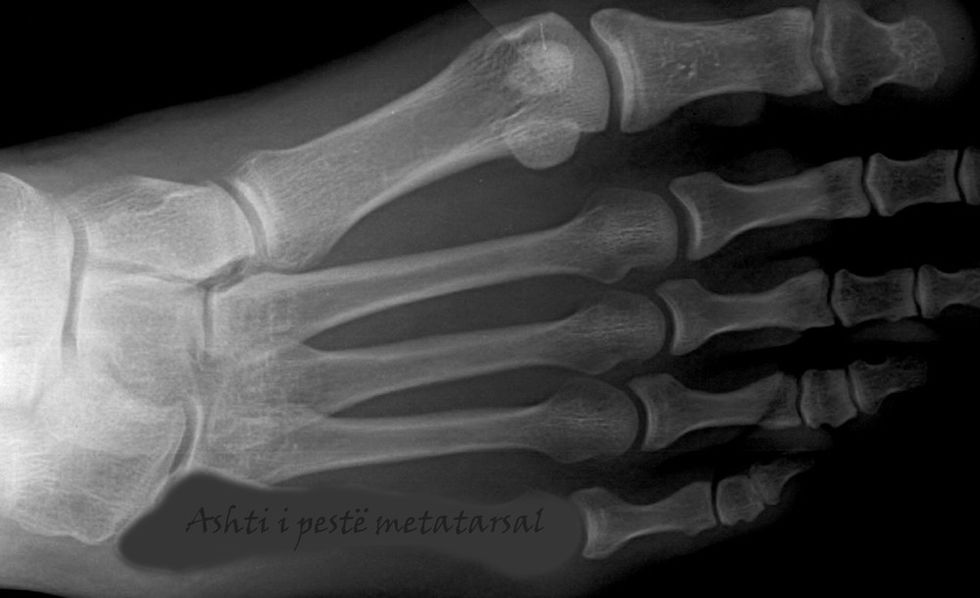

Ashti i pestë metatarsal

Ashti i pestë metatarsal është kockë e gjatë në këmbë dhe është i prekshëm në pjesën e jashtme të këmbës. Është ashti i dytë më i vogël nga pesë kockat metatarsale. Është kocka e gjatë në pjesën e jashtme të këmbës që lidhet me gishtin e vogël.